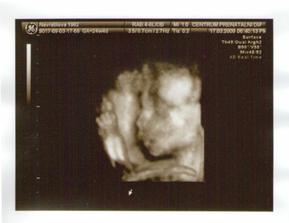

17.3. potvrzena na 3D holcicka 🙂